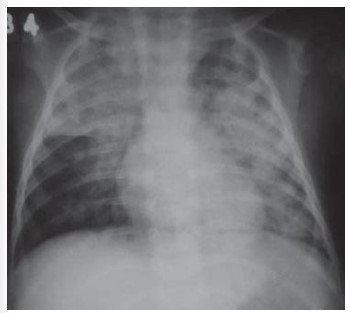

Abaixo é exposto uma radiografia de tórax, incidência anteroposterior, de um menino de 3 anos

de idade representando uma pneumonia não relacionada a anomalias anatômicas ou funcionais. A

criança está em tratamento de constipação com óleo mineral, como adjuvante. Observa-se na

imagem opacidades em ambos os pulmões, coalescentes, com distribuição dita em "asas de

borboleta". No contexto clínico, este aspecto permite o diagnóstico de:

Fonte: Oliveira GA, Del Caro SR, Bender Lamego CM, et al. Radiographic plain film and CT findings in pneumonia in infants following used in treatment of bowel obstruction by Ascaris lumbricoides. Pediatr Radiol. 1985;15:157-60.